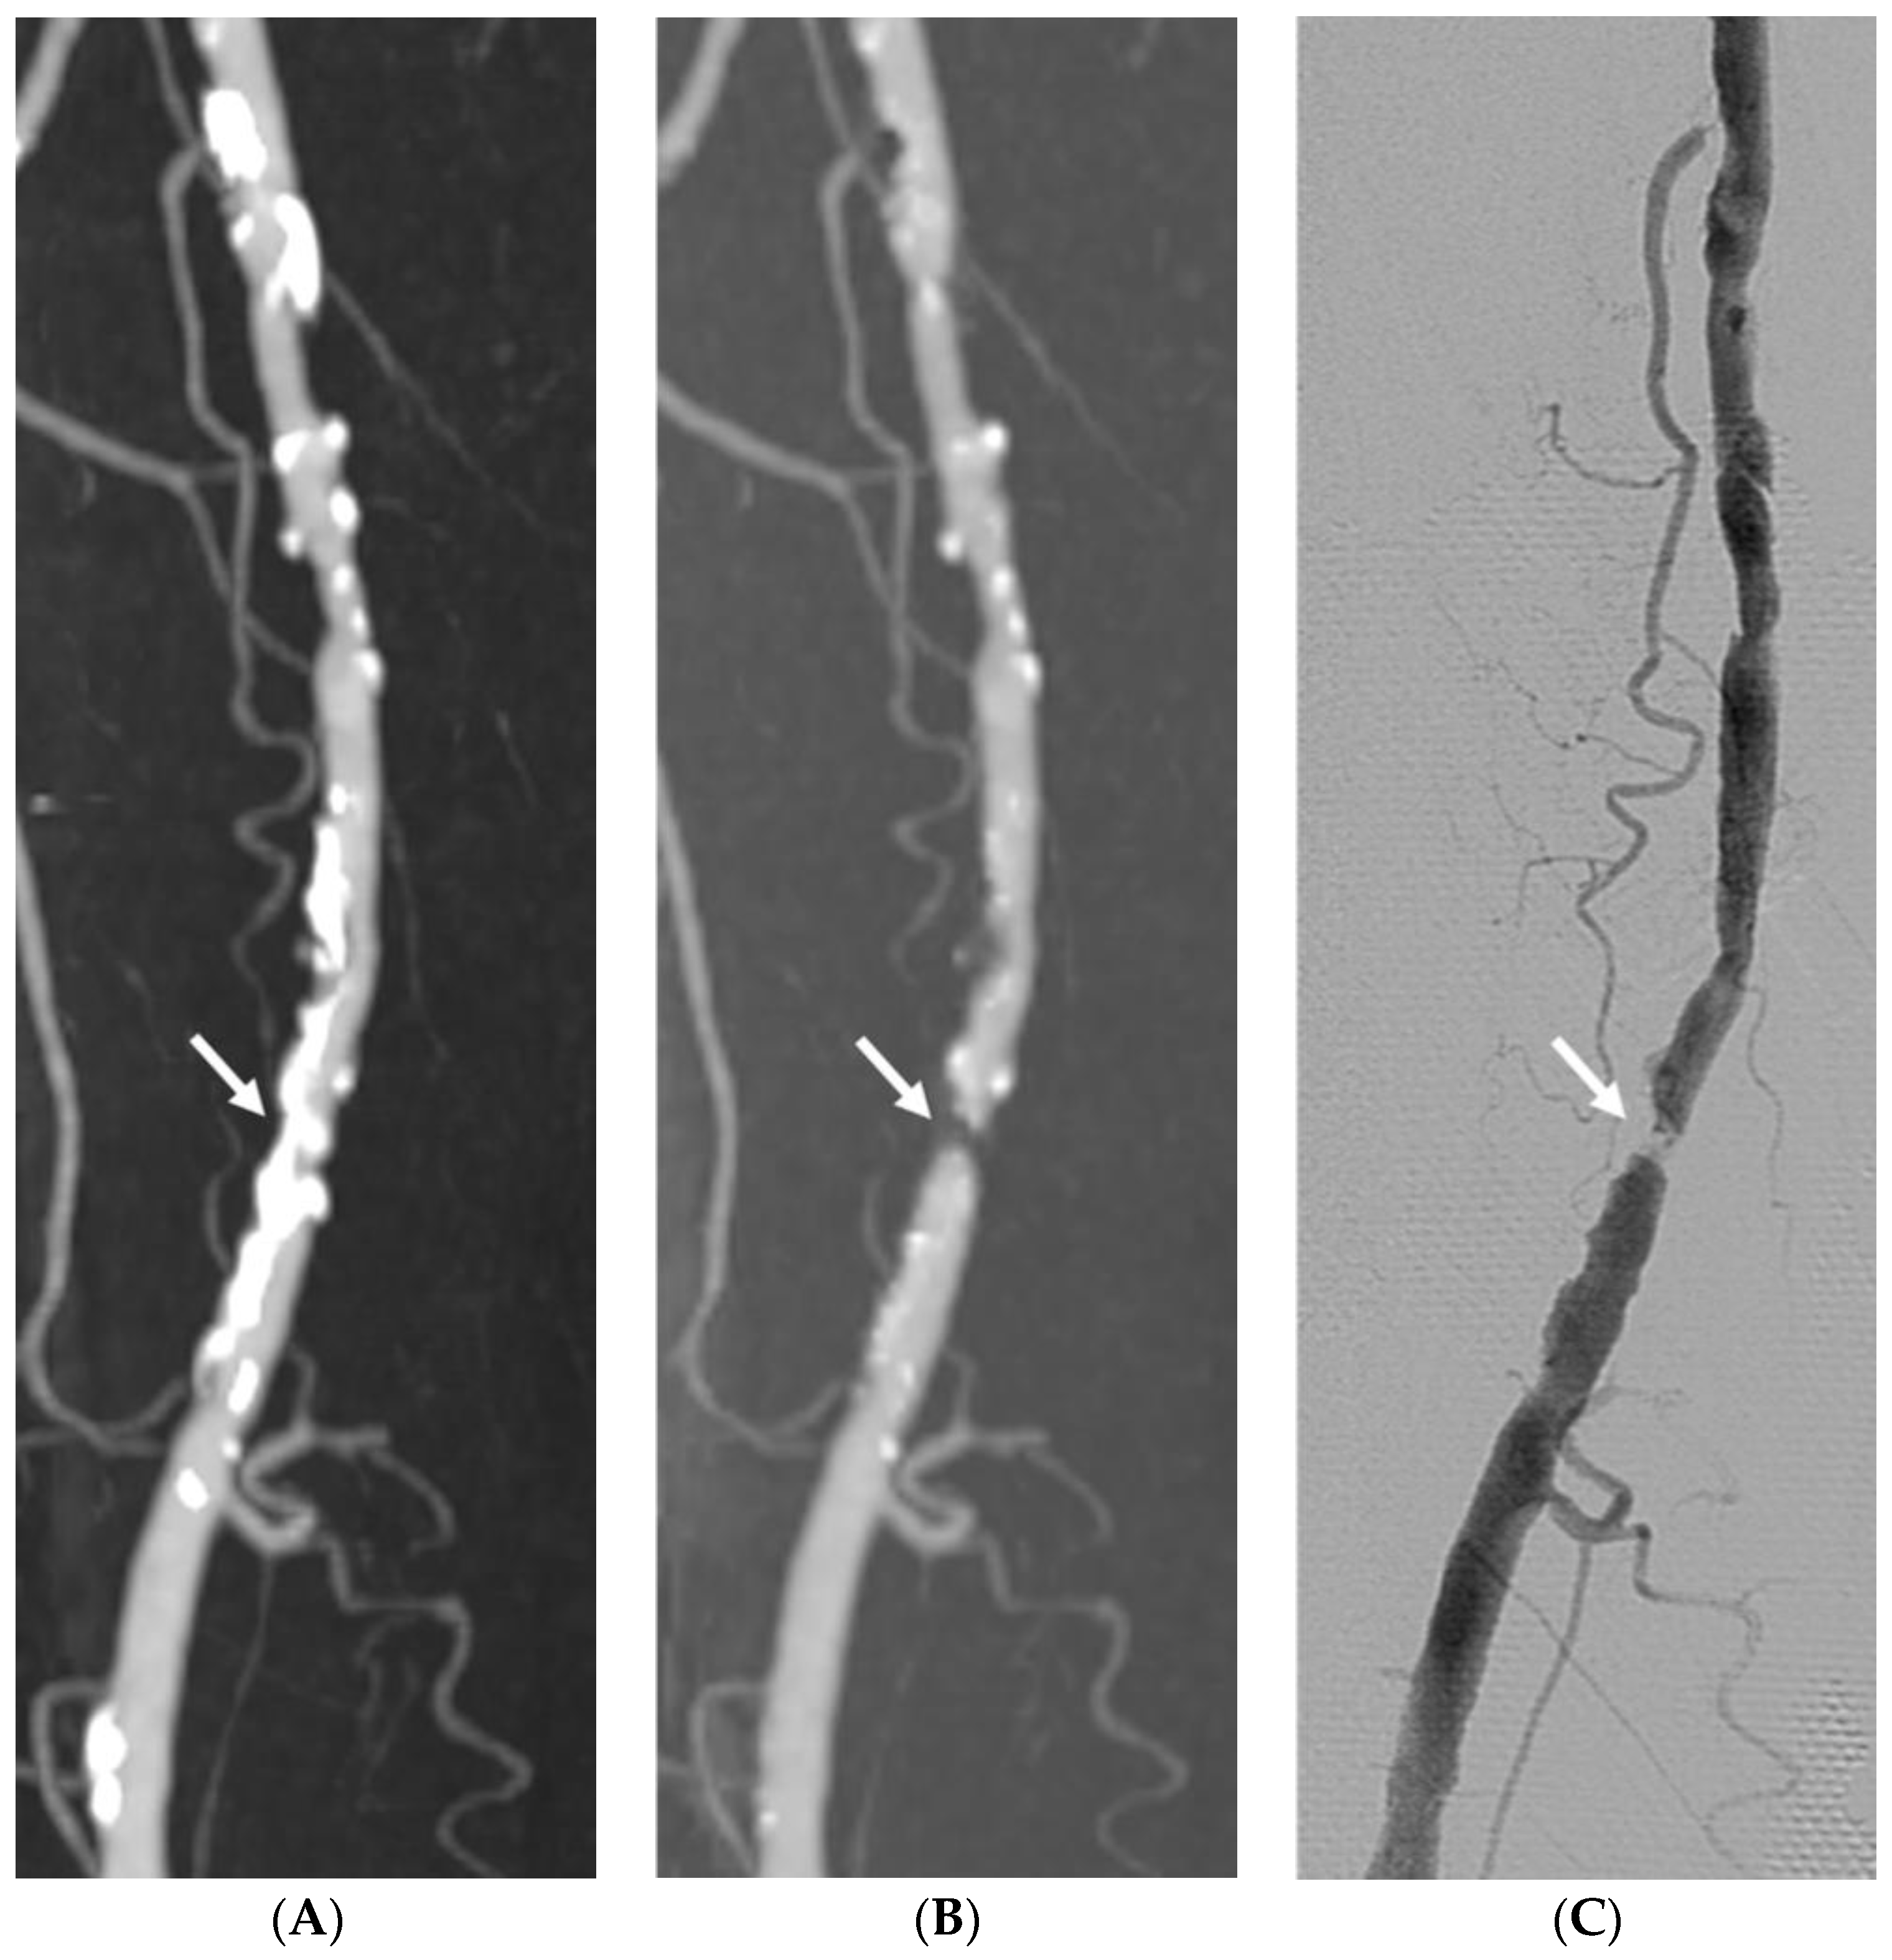

3.3. Impact of Vascular Wall Calcification